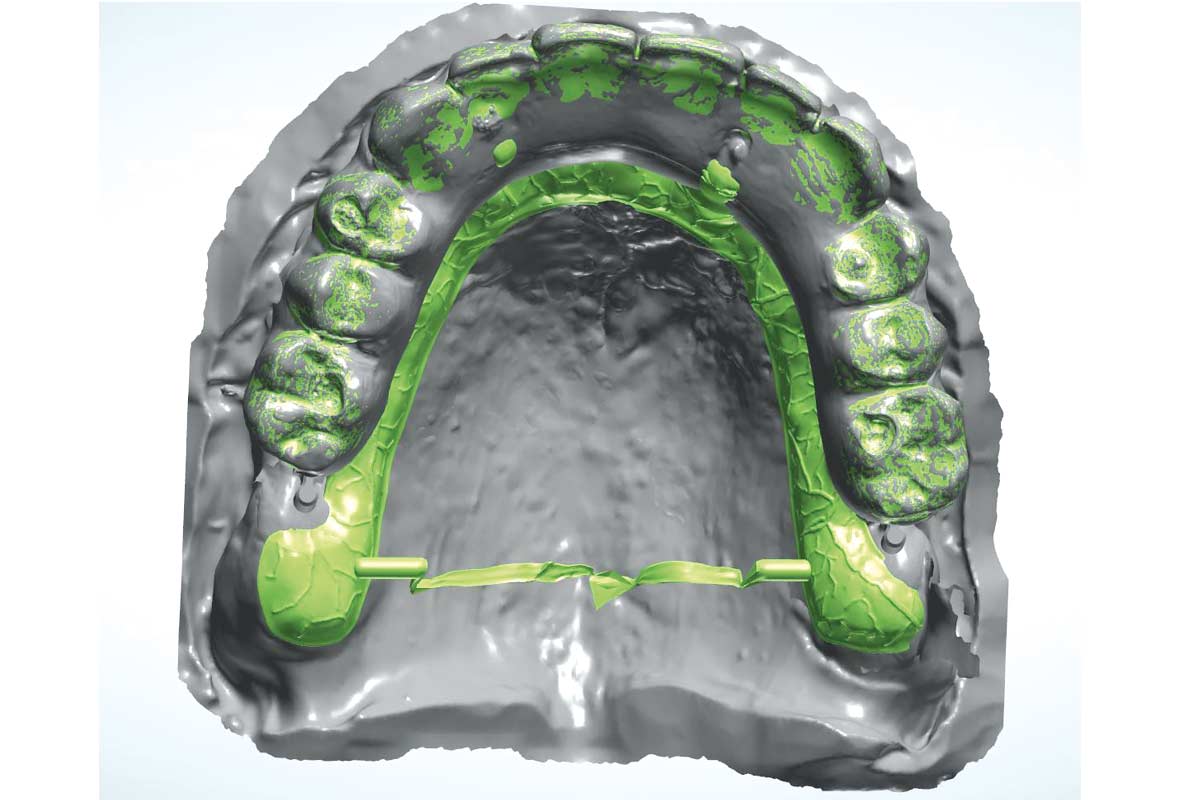

Loss of teeth in anterior maxilla caused by periodontitis